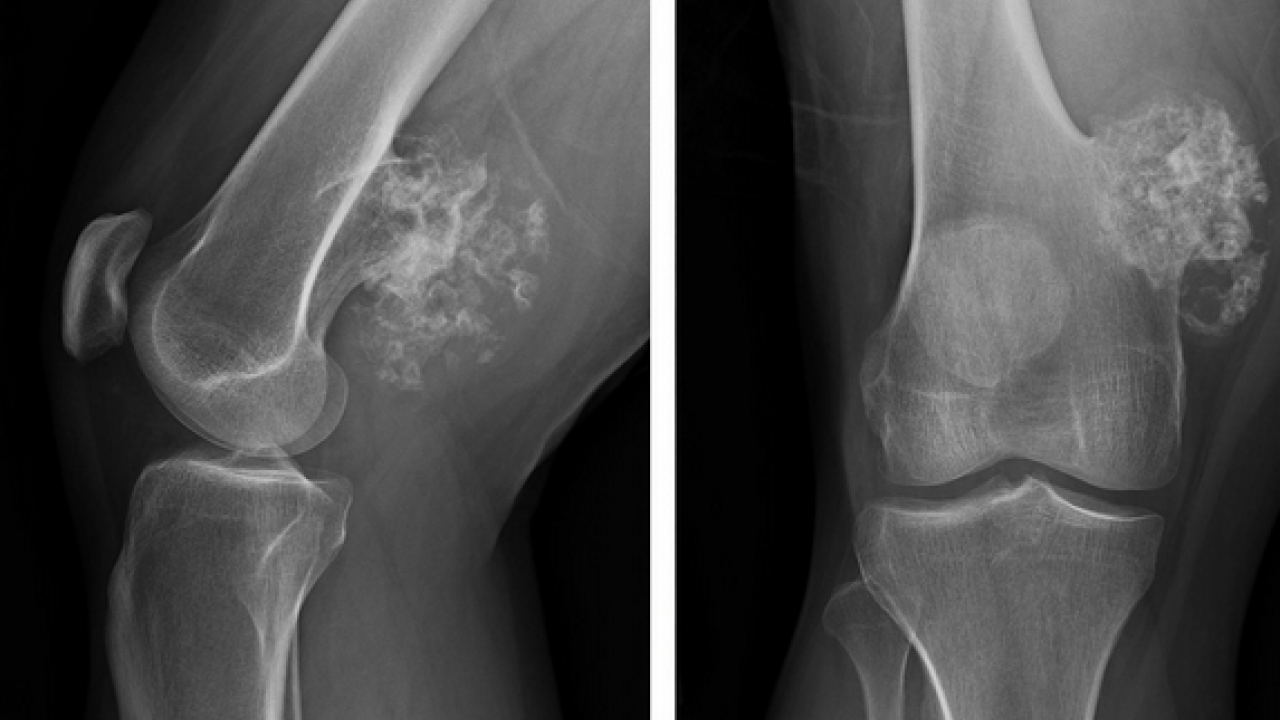

Cerrahi tedavinin, hastalığın türü, hastalığın evresi ve hastaya özgü klinik özelliklere göre kemoterapi ve radyoterapi ile desteklenebildiğini aktaran Doç. Dr. Muhammet Salih Ayas, tanı sürecinde ileri görüntüleme teknikleri ve biyopsi uygulamalarının büyük bir titizlikle yürütüldüğünü belirtti.

Doğru tanının, tedavi planlamasının en kritik aşamalarından biri olduğuna dikkat çekti.

Ameliyat sonrası oluşan kemik ve doku kayıplarının modern rekonstrüksiyon yöntemleriyle başarıyla giderilebildiğini ifade eden Ayas, "Biyolojik teknikler, hastaya özel geliştirilen protezler ve kemik transferleri sayesinde hem anatomik bütünlüğü yeniden sağlıyor hem de hastalarımızın fonksiyonlarını en iyi şekilde korumayı hedefliyoruz" diye konuştu.